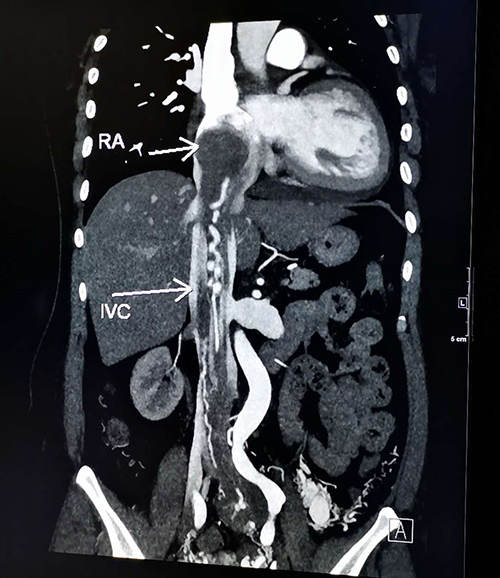

患者崔女士近一年来自觉活动后气短,近期因阴道大量流血前往省立医院妇科急诊就诊。紧急收入院后,妇科主任医师石敏、主治医师万吉鹏为崔女士进行了详细检查,发现崔女士患有盆腔静脉平滑肌瘤,并且已经顺着盆腔血管进入髂静脉、下腔静脉,“攀爬”到了右心房。崔女士同时还患有盆腔血管畸形——子宫动静脉漏,这是导致她阴道大量流血、重度贫血的主要原因。而巨大的静脉血管平滑肌瘤如果得不到及时治疗,心脏功能将受影响,随时有猝死的可能。

栓塞术后3天,崔女士进入复合手术室。妇科李长忠主任首先带领团队顺利切除崔女士子宫及盆腔静脉的血管平滑肌瘤。随后,血管外科董典宁主任医师、徐磊主治医师等将盆腔大血管的静脉平滑肌瘤仔细游离、切除。最后,心脏外科王正军主任医师、张骞副主任医师等建立体外循环,打开崔女士右心房,顺利将进入心脏的血管平滑肌瘤完整取出。手术耗时10余小时,术中患者血压曾一度下降到60/40mmHg,麻醉科张红斌主任医师、张文嘉主治医师及时进行输血、升压治疗,最终崔女士体内的静脉平滑肌瘤被一次性成功切除。目前,崔女士已经康复,出院后再次复查未见异常。